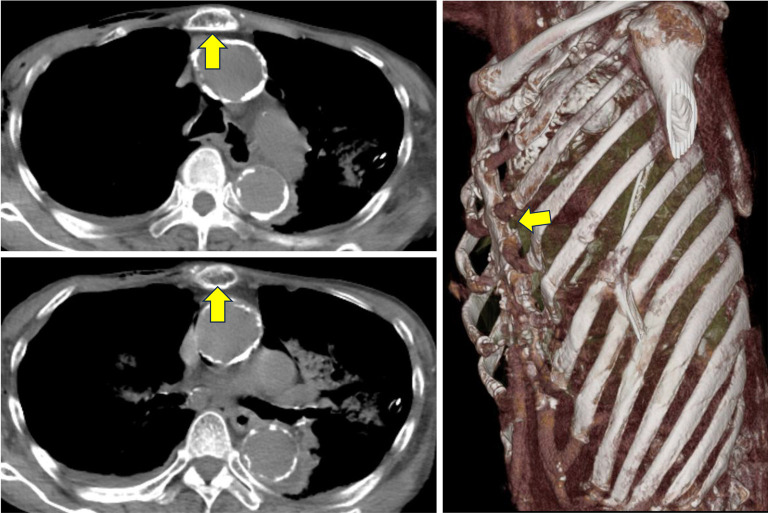

Case description: A 72-year-old woman presented to the emergency department with ventricular fibrillation caused by acute myocardial infarction. The patient underwent cardiac catheterization and coronary artery stenting following cardiopulmonary resuscitation (CPR). The patient was referred to Fukaya Red Cross Hospital owing to dyspnea caused by a flail chest following CPR. Being an elderly woman, the supporting tissues of the thorax had weakened, and she had a pronounced flail chest, a labored breathing pattern, and severe respiratory distress. Although there is the disadvantage that cardiac massage would become difficult, the cardiologist determined that cardiac function had stabilized after stent placement and that the likelihood of cardiac massage being necessary was extremely low, and therefore it was determined that repair using the Nuss method would be preferable. Two Nuss bars were inserted. Following the procedure, her respiratory condition improved, and she was discharged. Eight months later, the collapse of the anterior chest wall had resolved, and the Nuss bars were removed. However, the patient developed bilateral pneumothoraces post-removal. Thoracic drainage was performed, leading to improvement, and she was subsequently discharged.